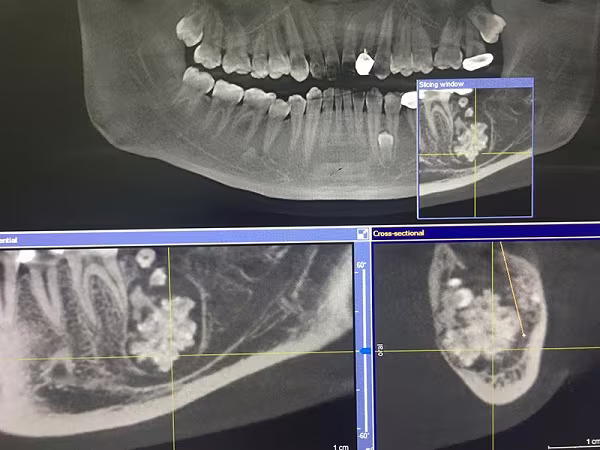

Hình ảnh X-quang cho thấy khối u chứa vô số răng nhỏ, dị dạng trong xương hàm của người bệnh

Trước đó, bệnh nhân này đến viện khám vì đau răng, sưng to gây biến dạng khuôn mặt. Tiếp hành chụp chiếu, các bác sĩ phát hiện trong khoang miệng bệnh nhân có khối u răng kích thước 3x4cm.

Đáng chú ý, đây là một khối u đa hợp gồm rất nhiều răng bé có đầy đủ tổ chức như một răng bình thường, kết lại thành một khối nằm sâu bên trong xương hàm, chiếm gần hết thân xương hàm.

Ekip phẫu thuật đã tiến hành bóc tách, cắt nhỏ từng phần khối u, sau đó từ từ gắp ra, tránh gây tổn thương dây thần kinh… Sau hơn 1 giờ phẫu thuât, các bác sĩ lấy ra được vô số răng nhỏ, dị dạng, kích thước to nhỏ khác nhau, có phần dính vào nhau, phần tách rời.